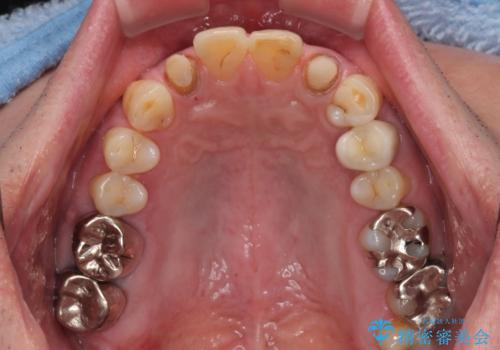

- 前歯の色味が気になるとのことで来院された患者様です。左上の2番目の歯の歯茎のラインと被せものの境目の適合が悪い状態だったのでオールセラミッククラウンによる補綴治療を行っていくことになりました。

金属の土台を外し、ファイバーコアを築造し、オールセラミッククラウンに適切な形に整えました。

左上の2番目の歯の型どりの段階で患者様より右上の2番目の歯も治療をしてほしいとのことで、根管治療(保険診療)、ファイバーコア、オールセラミッククラウンによる補綴治療を行いました。